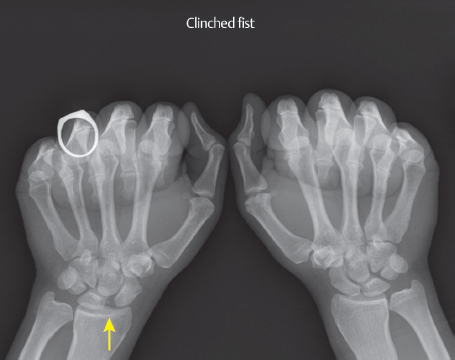

Patients are indicated for a Brunelli-type reconstruction if there is acute SL instability or subacute but reducible SL instability without development of SLAC changes. SL insufficiency or diastasis can be diagnosed by increased space between the scaphoid and lunate (► Fig. 68.3), flexed scaphoid, or extended lunate on lateral radiographs. 4